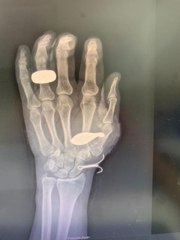

Şanlıurfa'da, düğününde halay çekerken maganda kurşuna hedef olan damat 22 yaşındaki Mustafa Alkan yaşamını yitirdi.